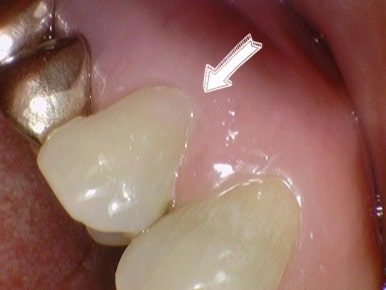

치경부마모 치료법 레진 전후 사진

치경부마모증의 치료법은 여러가지가 있는데 가장 흔한 치료법은 레진치료입니다. 그 패인 부위를 레진으로 떼우는 것입니다.

치경부 마모 가 있어서 시린 환자분의 치아를 레진으로 떼운 사진을 볼게요. 저희 치과에서 직접 치료하고 찍은 사진이랍니다.

치경부 마모 레진 치료 전 후

시린 치아 마모 레진 전후

치경부가 패여서 물과 양치질에 의해 시리거나, 찬바람을 쓰읍하고 들이마시기만 해도 시릴 수 있어요. 이런 경우 위와 같이 레진으로 때우면 그 증상은 대부분 사라지게 됩니다.

치경부마모가 있는데 정말 심해서 치아신경까지 노출된 경우라면 그때는 레진이 아니라 신경치료를 해야하니 증상이 있으신 경우 꼭 치과에서 치료하실 치과의사와 상담한 후 치료를 결정하시길 바랍니다.